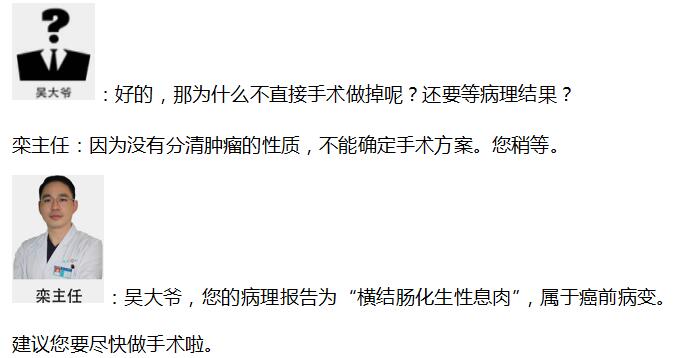

�����������֮�������ʾ���ү�����˳�Ϣ�⣬Ŀǰ��û���ֶ�����

���� �����˹�ͨ�����ү�������������ƣ� ����������ǰ����������20����������ξͿ�ʼ�����ү����������������ȡ����HCPT�����������Сʱ������Բ���ɹ�����Ϊ���ү�Ľ᳦Ϣ������ʱ���Ѿ��ܳ��ˣ�����Ҫ��Ժ�۲켸�죬���ܳ�Ժ������Ҳ������˷���������Ҫһ����һ�θ��飬��ֹ���䡣